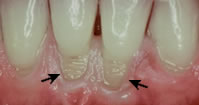

Abrasion

abrasionAbrasion is the wearing away of tooth enamel by a foreign object. Common causes of abrasion are: